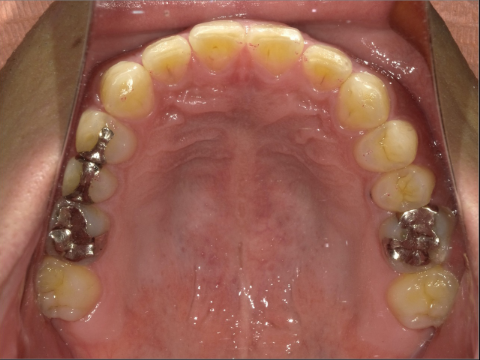

ご年齢 35歳男性

治療期間 2022/08/22〜2023/03/24(1年5ヶ月)

診断 110,000円(税込)

アライナー 550,000円(税込)

リテーナー 55,000円(税込)

BEFORE

AFTER